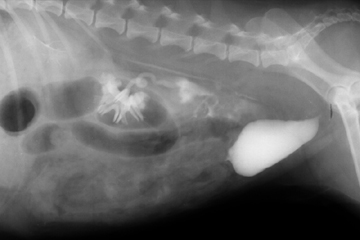

A lateral view of an IVP. Notice the contrast medium leaking from the ruptured ureter.